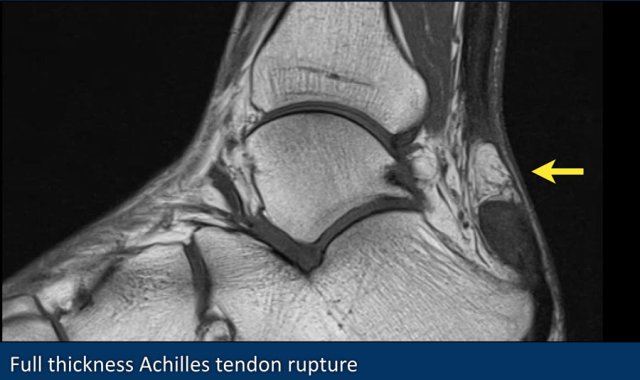

Rupture of the Achilles tendon usually occurs in the part of the tendon situated within 6 centimeters of the insertion to the calcaneus.

This part is prone to rupture because the blood flow in this area is poor, which also can impair its ability to heal.

The image shows an old rupture.